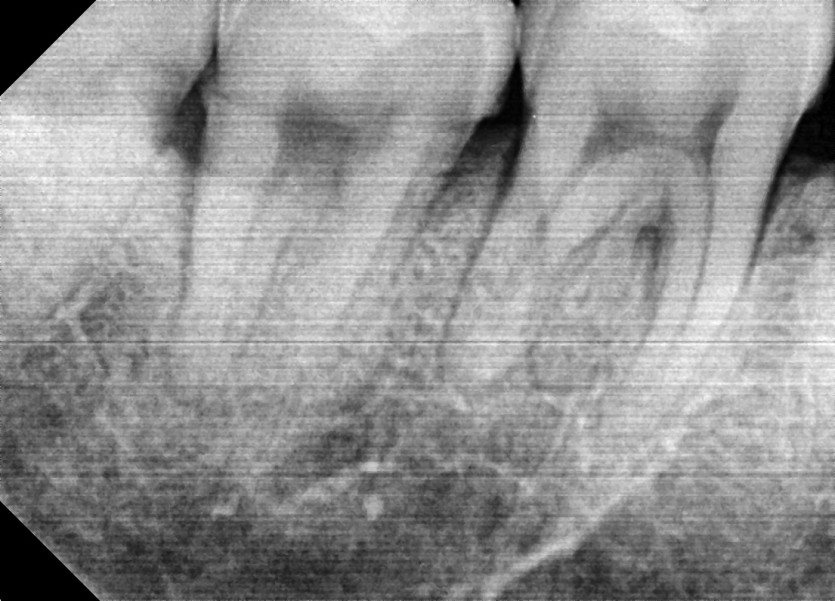

#48 사랑니 발치

구강외과 전문의가 당일발치 했습니다.